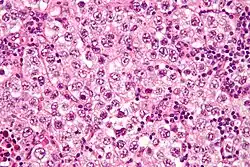

| Micrograph of a seminoma, a common germ cell tumor. | |